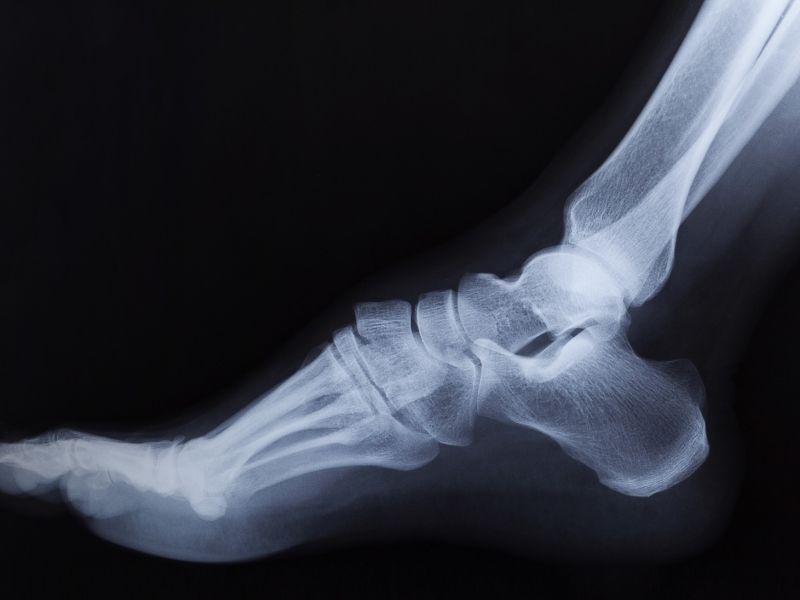

Ayak ve ayak bileğinin stres kırıkları son yıllarda oldukça sık görülen ortopedik problemlerden biridir. Gerilim kırıkları, aşırı kullanımdan kaynaklanan incinmeler sonucu oluşan kırık tipidir. Kaslarınız yorulduğunda, bu minicik çatlaklar, kemiklerinizde gelişir ve tekrarlayan çarpma şoklarını, daha fazla absorbe edemez (ememez). Bu durum olduğunda, kaslar gerilimi, kemiklere; küçük bir çatlak veya kırık yaratarak transfer ederler.

Pek çok gerilim kırıkları, ayak kemiklerine ve alt bacağa aşırı yük bindirilmesinden ortaya çıkar, En çok etkilenen taraf,orta ayak ile ayak parmakları arasında yer alan, ayağın ikinci veya üçüncü uzun kemikleridir (metatarslar ).Gerilim kırıkları, topukta, alt bacağın dış taraftaki kemiğinde( fibula da ) ve orta ayağın tepesinde bir kemik olan naviküler kemikte de olur.

Gerilim kırıklarını, kırık gerçekten iyileşmeye başlayıncaya kadar, röntgende görmek zordur. Ortopedistiniz, röntgenden daha hassas olan ve gerilim kırıklarını erken ortaya çıkaran, bir kemik taraması isteyebilir.